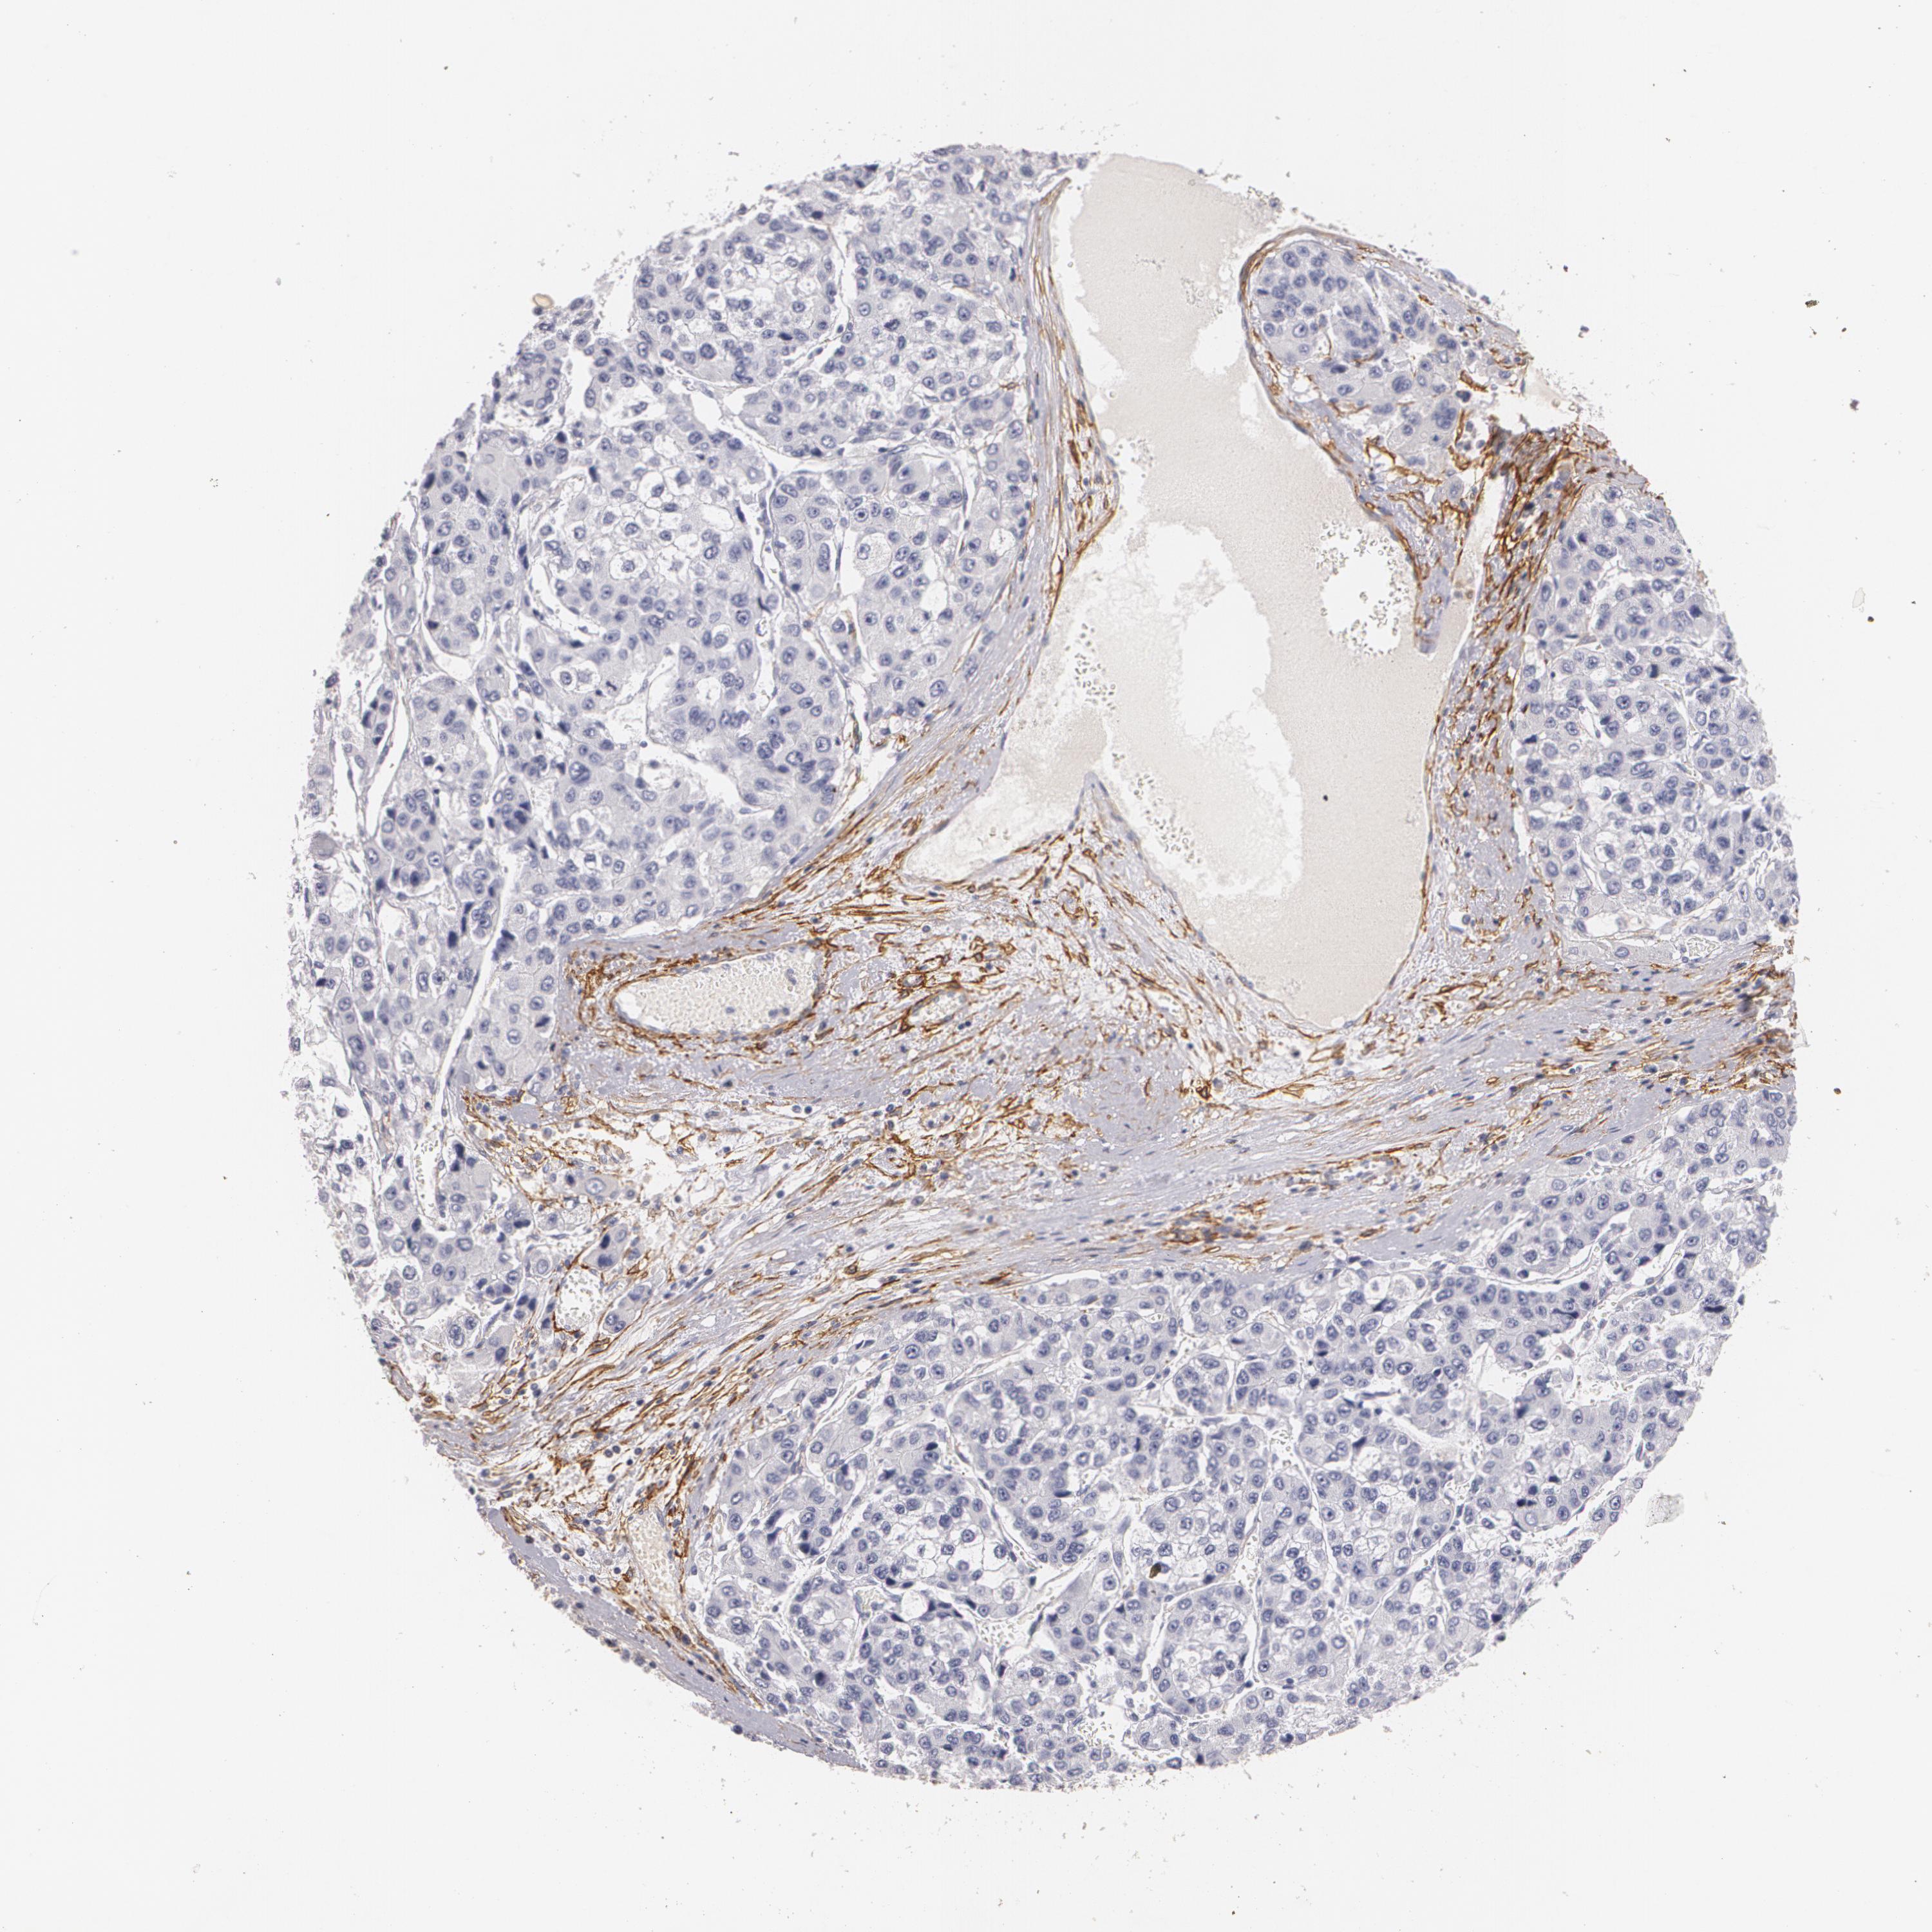

LIVER CANCER - Protein expressioni

A mouse-over function shows sample information and annotation data. Click on an image to view it in a full screen mode. Samples can be filtered based on level of antibody staining by selecting one or several of the following categories: high, medium, low and not detected. The assay and annotation is described here.

Note that samples used for immunohistochemistry by the Human Protein Atlas do not correspond to samples in the TCGA dataset.

Antibody stainingi

Antibody staining in the annotated cell types in the current human tissue is reported as not detected, low, medium, or high, based on conventional immunohistochemistry profiling in selected tissues. This score is based on the combination of the staining intensity and fraction of stained cells.

Each image is clickable and will lead to virtual microscopy that enables deeper exploration of all samples and also displays staining intensity scores, fraction scores and subcellular localization as well as patient and tissue information for each sample.

Antibody HPA004765

Antibody CAB000143

Antibody CAB001995

Staining

High

Medium

Low

Not detected

Intensity

Strong

Moderate

Weak

Negative

Quantity

>75%

75%-25%

<25%

None

Location

Nuclear

Cytoplasmic/membranous

Cytoplasmic/membranous,nuclear

Cholangiocarcinoma

Carcinoma, Hepatocellular, NOS